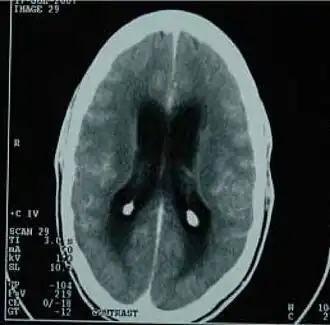

![]() Tomografický snímek ukazující tuberkulózní zánět mozkových blan | |